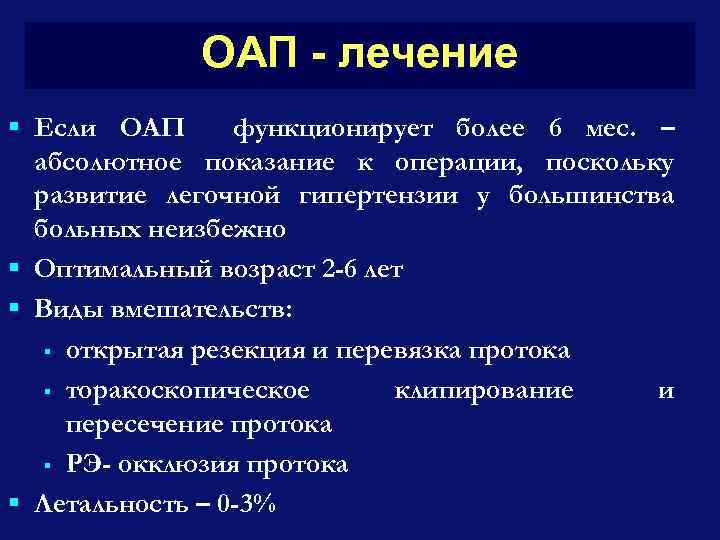

ОАП - лечение § Если ОАП функционирует более 6 мес. – абсолютное показание к операции, поскольку развитие легочной гипертензии у большинства больных неизбежно § Оптимальный возраст 2 -6 лет § Виды вмешательств: § открытая резекция и перевязка протока § торакоскопическое клипирование и пересечение протока § РЭ- окклюзия протока § Летальность – 0 -3%